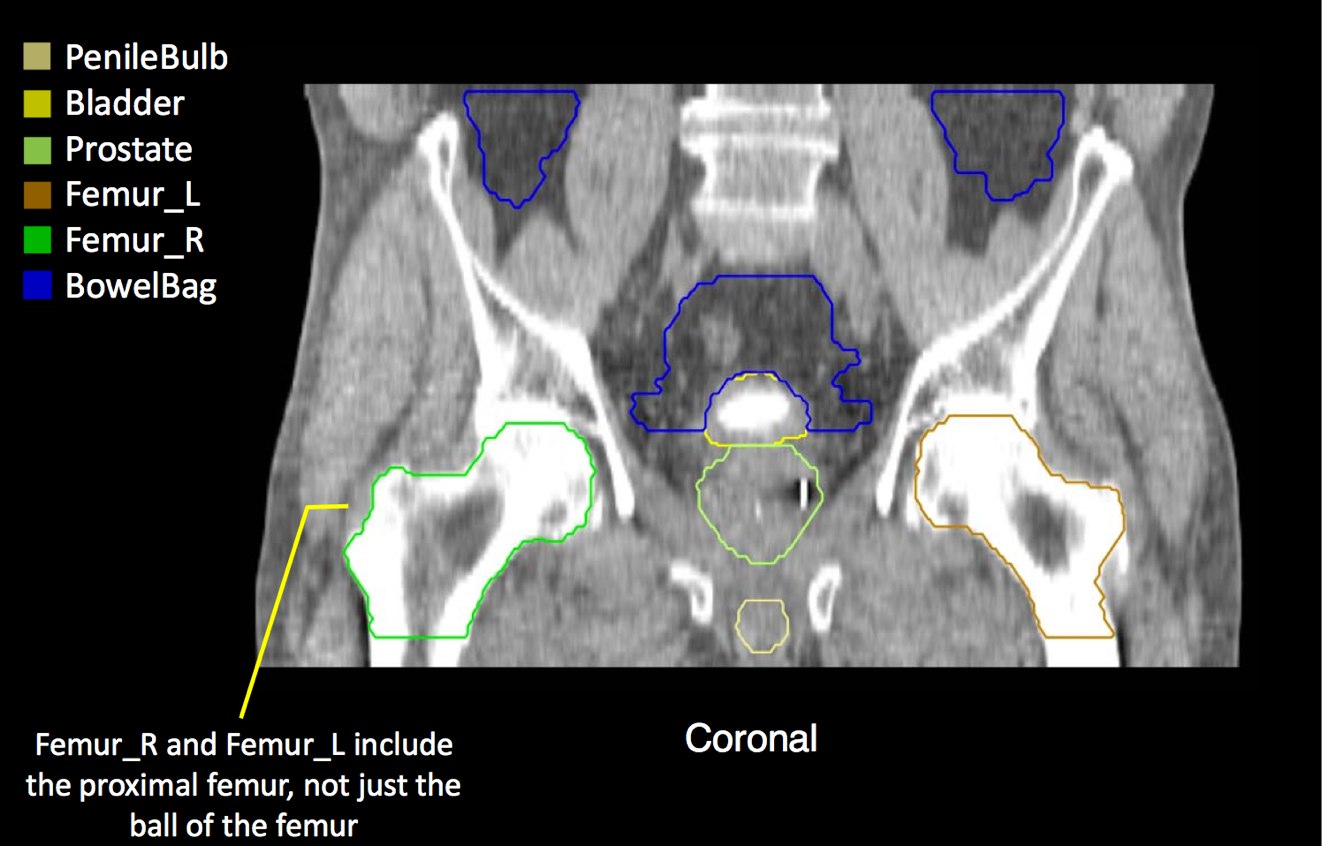

At a minimum, the following contours should be available to the planners:

• prostate

• seminal vesicles (treat at least proximal if risk calculated > 15% --ucsf)

• pelvic lymphatics (if treatment indicated -- risk > 15% -- ucsf)

• femoral heads

• rectum

• bladder

• bowel (where necessary due to bowel prolapsing below the bladder)

• penile bulb

There is significant variation of contours and techniques. The apex and base are regions most susceptable to variation. 3D perspectives help signficantly reduce this variation using transverse, sagital and coronal projections to determine the true extent of the prostate. More recently contouring atlases have been developed by the RTOG with grant assistance from the NCI and are available here. The following images are obtained from the RTOG contour atlases as an excerpt demonstrating areas of potential uncertainty.

GTV is the entire prostate. If a urethrogram is used, the apex is designated at the visualized prostate or 5 mm superior to the tip of the urethrogram dye. The initial field encompasses the pelvic lymphatics from L4/L5, pre-sacral nodes from L5-S1 and inferiorly below the prostate by 5 mm. The internal and external iliac nodes should be covered below the SI joints. Lateral fields should include the posterior extension of the seminal vesicles. The usual posterior border is S2/S3, but this may vary based on CT imaging and imaging should take precedence. The inferior extent of the internal iliacs are the tops of the femoral heads, the inferior extent of the obturator nodes is the top of the pubic symphysis.

CTV construction is a selective expansion on the prostate GTV. For the lymphatic portion of treatment, the CTV should be a 7 mm expansion around the contoured vessels, corrected for anatomical barriers. The nodal CTV expansion should not extend outside of the true pelvis, into muscle, bone or organs such as bladder, rectum and bowel. Treatment will be to the PTV planning target volume which will consist of a minimum of 0.5 cm expansion on the CTV and a maximum expansion of 1.5 cm in all dimensions.